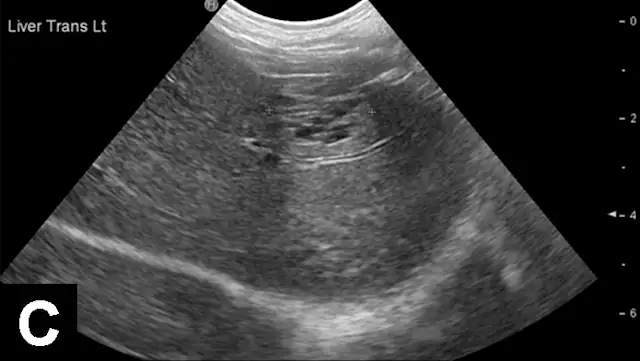

Figure 2A

Liver with normal parenchymal echogenicity in a dog (A); however, cytologic examination via fine-needle aspirate showed diffuse infiltration of malignant mast cells. Liver with normal ultrasonographic appearance in a cat (B); however, cytologic examination via fine-needle aspirate showed diffuse infiltration with lymphoblasts indicative of lymphoma.